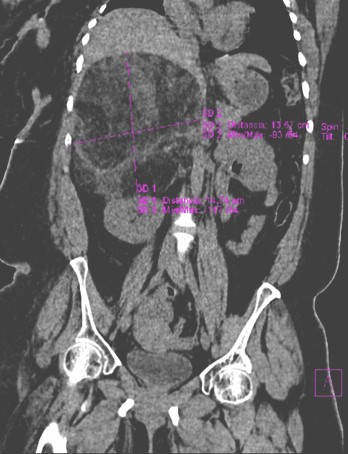

Ecografía abdominal con riñones de tamaño y morfología normal, objetivándose masa en suprarrenal derecha de 12x10 cm, hiperecoica, heterogénea, bien delimitada, compatible con mielolipoma. Se confirmó mediante TC, que mostraba una masa ovalada, bien delimitada, extensa, mixta en proyección de la glándula suprarrenal derecha con densidad predominantemente grasa de -114 UH de 14,7 x 13,6cm entre el hígado y el riñón derecho que impresiona depender de la glándula suprarrenal que provoca desplazamiento del riñón hacia abajo y se acompaña de componente sólido, formando pseudotabiques sin calcio ni signos de sangrado.

MIELOLIPOMA SUPRARRENAL GIGANTE (figura 1)